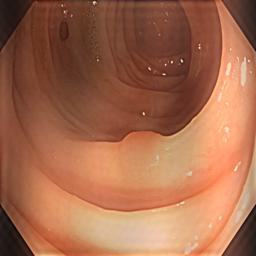

As Fig. 2(c) shows, background inference (shadows) is introduced by the Fourier-Transform-Based domain generalization. In our ICASSP-2024 study [25], we applied soft-thresholding (ST) filtering to minimize background interference in retinal fundus image segmentation. Soft-thresholding, a widely recognized technique in signal processing and statistical estimation, promotes sparsity and enhances data quality [26, 27]. By applying a threshold to the DFT coefficients, it effectively reduces noise and irrelevant details while preserving essential features. The soft-thresholding function operates for a given threshold as follows:

where is the input and is the threshold value. However, when we applied the same domain generalization method [25] on the polyp dataset, we notice that the soft-thresholding function enhances noisy patterns while eliminating the shadows caused by the target background, as Fig. 2(d) present. This is because the soft-thresholding function shrinks all coefficients (both large and small) toward zero. This introduces bias in the retained large coefficients, potentially distorting important features.

As Fig. 2(d) reveals, applying hard thresholds removes shadows caused by the amplitude swapping without producing noisy patterns, but it may smooth the synthetic images.